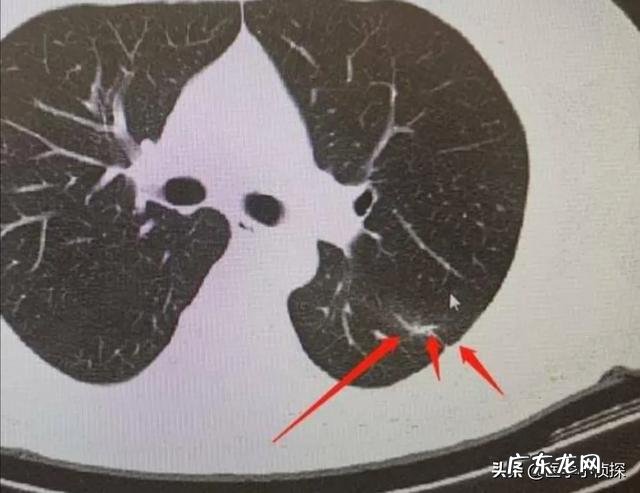

第二个 , 也是大家特别熟悉的肺结节 。体检查出肺部小结节的比例高达20-30% , 而对于吸烟人群 , 这种检出率更高 , 接近50% , 而我们国家有3亿以上的烟民;

先讲一下大家最为熟悉的肺结节 。首先 , 大家要记住 , 一般我们说的肺结节 , 指的都是≤3cm以下的结节 , 对于超过3cm的结节 , 我们就不再叫它结节了 , 而是称之为肿块 。

而且拍片发现肺结节 , 本身不能说我们得了什么病 , 因为肺结节只是我们影像学上的一种表现 , 并不代表这个结节具体会是个什么东西 。只是对于我们正常人来说 , 不应该有结节 , 因此结节的出现肯定代表我们的肺部有病变 , 但具体它是什么 , 是良性的 , 还是恶性的 , 需要进一步的来区分 。只不过 , 一般情况下 , 在影像下我们统称这些都叫肺结节 。

假如你胸部CT检查出肺结节 , 重点关注报告单上这些内容 , 基本上不用过于担心肺结节最后会发展为晚期肺癌!